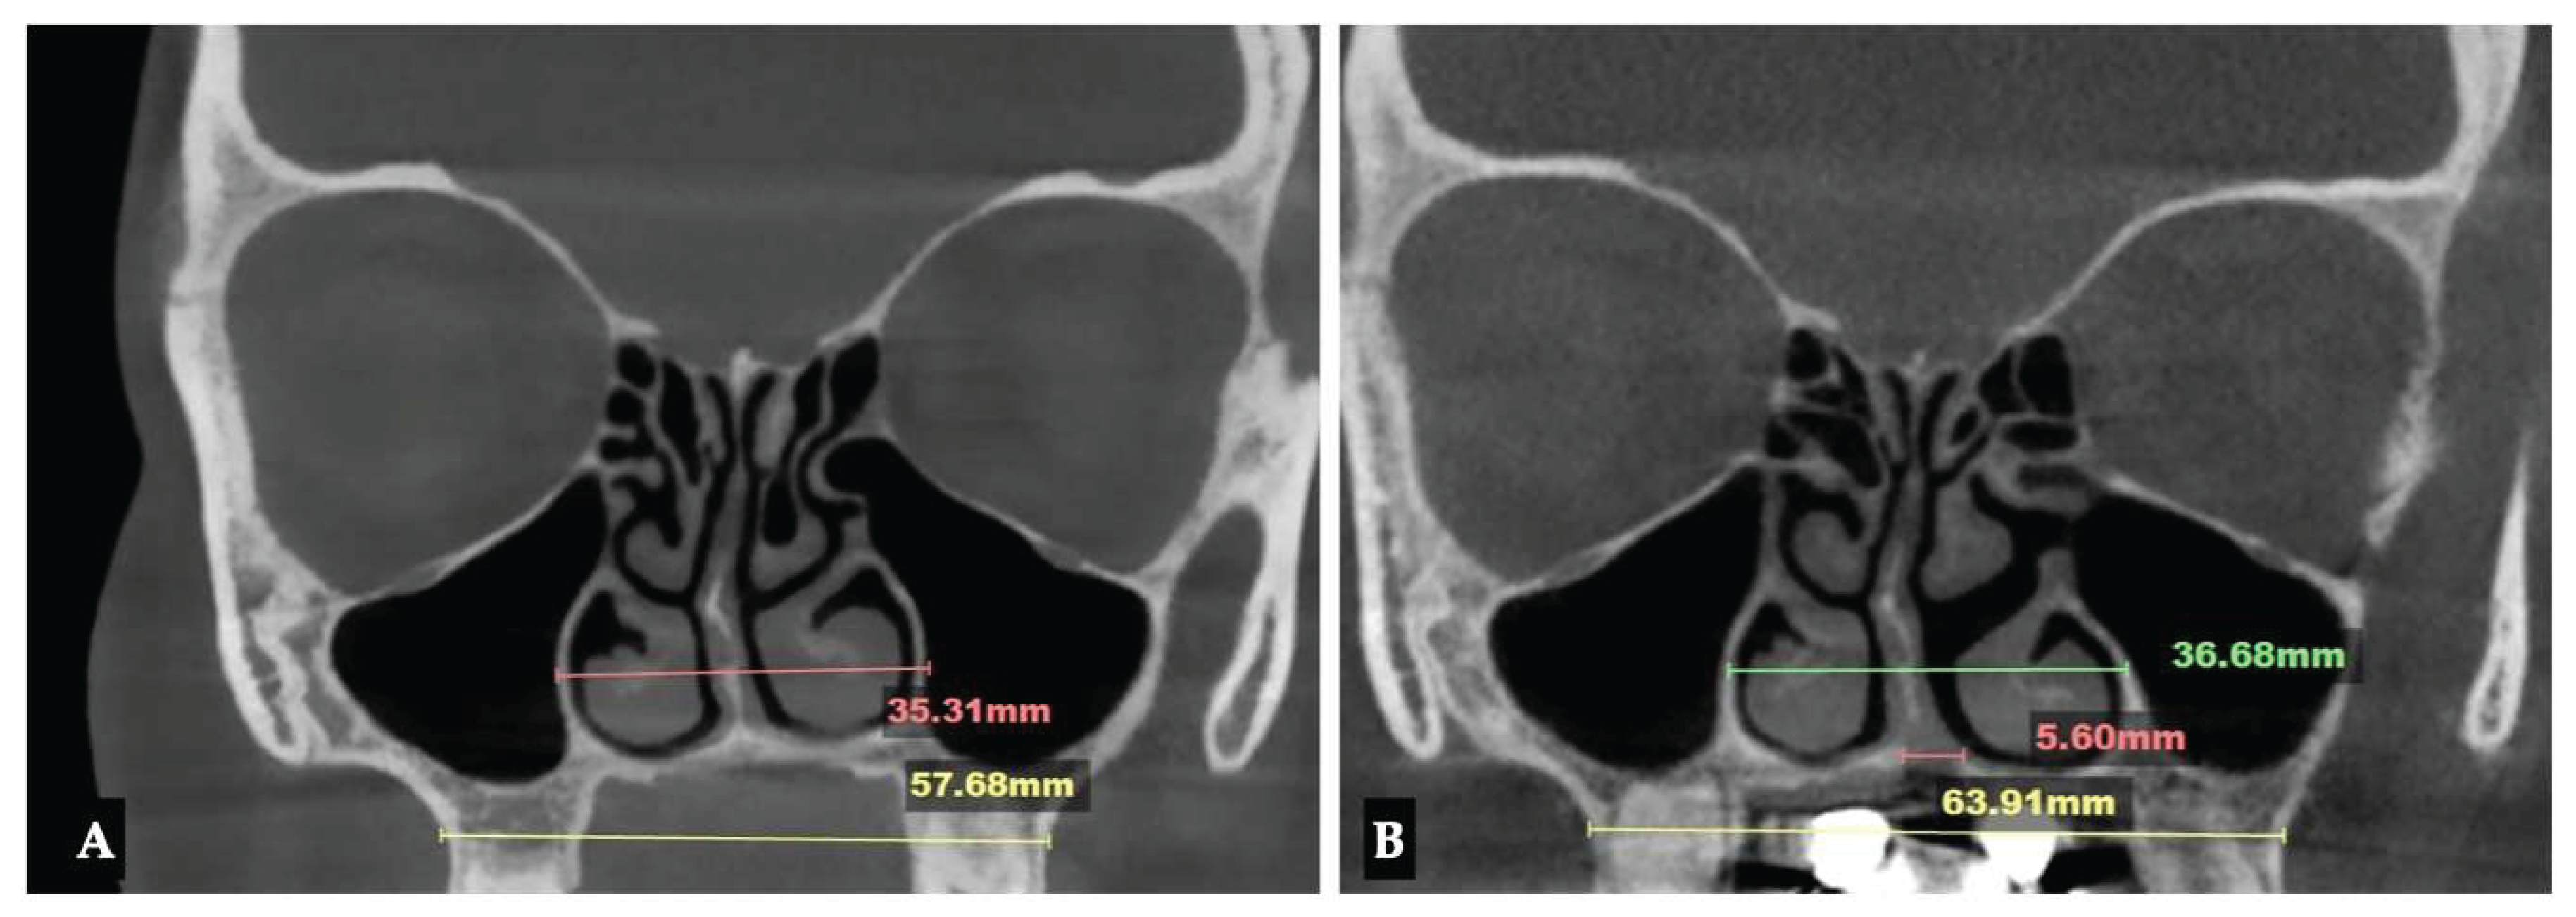

Background: While mini-screw-assisted rapid palatal expansion (MARPE) is effective for correcting maxillary transverse deficiency in adults, perimaxillary suture disarticulation—particularly at the pterygomaxillary junction—can be inconsistent. This study evaluates skeletal and dentoalveolar outcomes of a novel 3D-guided midpalatal piezocorticotomy-assisted MARPE protocol, focusing on expansion symmetry and pre-existing asymmetries. Methods: Three adult patients were retrospectively analyzed after treatment with 3D-guided midpalatal piezocorticotomy-assisted MARPE expansion and one with non-guided midpapalatal piezocorticotomy and MARPE expansion. Surgical guides were digitally designed using CBCT data to align with the nasal septum orientation in multiple planes. Perimaxillary suture disarticulation was measured pre- and post-expansion, and dentoalveolar changes were evaluated. Post-expansion asymmetries were addressed using directly printed aligners. Results: Complete midpalatal suture separation (mean 8.48 mm), involving both anterior and posterior nasal spine regions, was achieved in one patient. Bilateral pterygomaxillary disarticulation averaged 1.06–1.23 mm, resulting in forward–outward rotation of the nasomaxillary complex. Additional separation occurred at the frontonasal (2.03 mm) and vomeromaxillary (1–2 mm) sutures, with no significant changes in orbital or peri-orbital sutures. One patient presented with pre-existing dentoalveolar asymmetry, which intensified the perceived post-expansion imbalance but was successfully corrected with directly printed aligners. In the second case, 5.6 mm of suture separation resulted in a limited lateral nasal width increase (<1.5 mm), while maxillary base expansion exceeded 6 mm. A significant canine plane cant (1.2 mm) and divergent axial inclinations of the maxillary central incisors relative to the palatal plane were also observed. In the second case, a non-impactful palatal bone fracture with asymmetric displacement of the left palatine fragment was documented. After 16 months of aligner therapy, all cases exhibited favorable remodeling of the palatal structures, midpalatal suture, and alveolar processes, accompanied by improved dental alignment, occlusal plane symmetry, and mandibular dentoalveolar adaptation. The dento-alveolar expansion achieved in the third case over the course of 16 months of treatment was approximated at 4 mm. The fourth case showed consistent improvement with direct printed aligners after MARPE midpalatal diasrticulation of 11 mm after experiencing minor bone fracture. Conclusions: Human skulls exhibit considerable variability between the left and right sides, which can influence spatial balance. Pre-existing cranial asymmetries appear to be the primary contributors to asymmetry following MARPE treatment. Careful evaluation of dentoalveolar discrepancies and axial tooth inclinations is essential for preventing and managing potential asymmetric dental arch outcomes during the post-expansion phase. Although peri-maxillary bone fractures are relatively uncommon, their occurrence is influenced by multiple factors. Adjunctive techniques, such as 3D-guided midpalatal piezocorticotomy, show promise in significantly lowering the risk of intra-expansion peri-maxillary fractures.

| Suture nomenclature | Amount of disarticulation |

|---|---|

| Midpalatal | 8.48 mm |

| Palatinomaxillary (transverse) | none |

| Nasomaxillary | 1-2 mm |

| Zygomaticomaxillary | none |

| Lacrimomaxillary | none |

| Ethmoidomaxillary | none |

| Sphenomaxillary | none |

| Vomeromaxillary | 1-2 mm |

| Frontomaxillary | 2.5 mm |

| Pterygomaxillary | 1.06-1.23 mm |

| Frontonasal | 2.03 mm |

| Frontozygomatic | None |